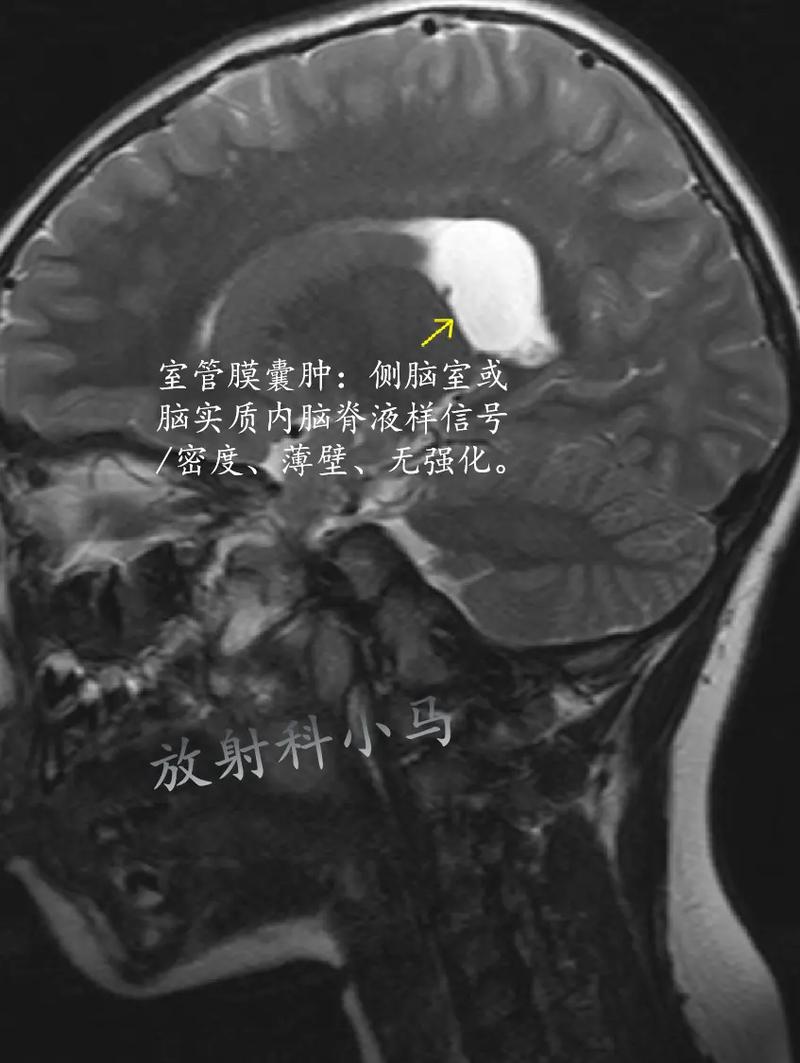

- 室管膜:这是大脑内部和脊髓内壁的一层薄膜,它的主要功能是产生脑脊液,并保护中枢神经系统,可以把它想象成大脑内壁的“壁纸”或“内衬”。

- 囊肿:是一个充满液体或半固体物质的“小水泡”或“囊袋”,在脑部,绝大多数囊肿是良性的,意味着它们不是癌症,不会扩散。

在新生儿大脑右侧的室管膜(脑内壁)上,出现了一个充满液体的良性囊袋。